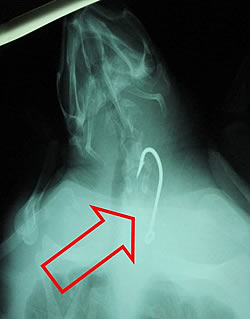

Λίγες ημέρες μετά, η ακτινογραφία που έγινε στην «Αρσίδα» αποκάλυψε ένα αγκίστρι από παραγάδι το οποίο και αφαίρεσε η κτηνίατρος του Κέντρου. Η εξέλιξη της παρακολουθείται στενά από τους ειδικούς του Κέντρου μιας και είναι άγνωστο προς το παρόν πως θα αντιδράσει ο οργανισμός της στις ποσότητες πλαστικού από την μεσινέζα που είχε καταπιεί. Ευελπιστούμε ότι θα μπορέσει να αποβάλλει το ξένο σώμα από μέσα της και να αναρρώσει πλήρως.